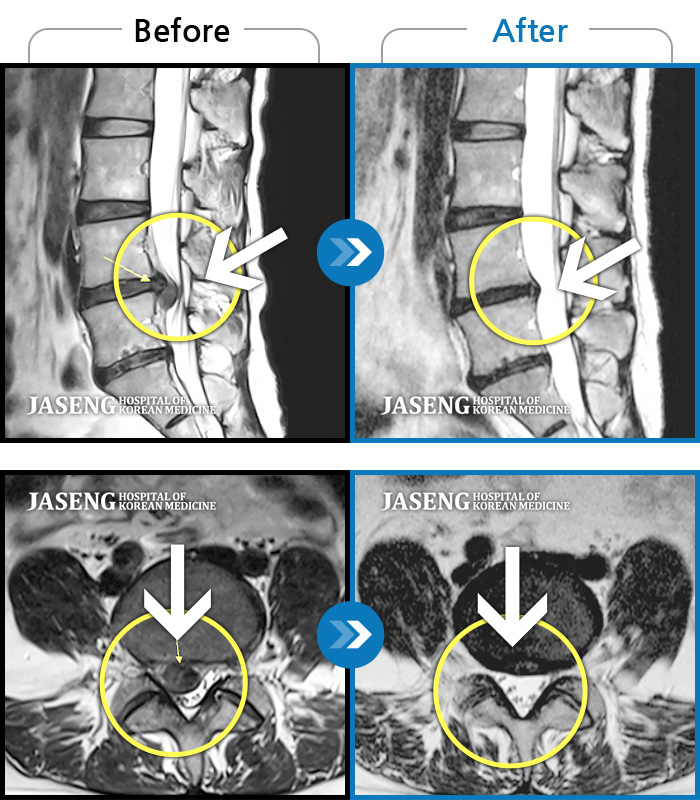

40대 초반 여성 환자인데요,, 처음 선생님 뵈었을 때에 1번,4,5번허리디스크 증상도 증상이지만,

본인 나이에 비해서 10~15년정도 퇴행이 많이 되어있어서 전체적으로 관리가 많이 필요하다고 설명해주셨구요,,

그당시 원장님진료실에서 보았던 저의 엠알아이사진이 아직도 생생히 기억이 납니다 ^^

뼈부분의 색이 왜저렇게 검냐고 여쭈어 보았더니, 말씀주신데로 "퇴행이"많이 되어서 그렇다고 설명해주시면서,,

그렇다고 당장 크게 머가 안좋거나 그런건 아니고,, 퇴행된 뼈자체를 새것으로 되돌릴수는 없지만,,

꾸준히 치료받으면서 관리만 잘한다면 건강한 뼈를 가진 사람과 동일하게 건강한 생활 충분히 가능할수 있다고,, 긍정적으로 말씀을 주셨어요...